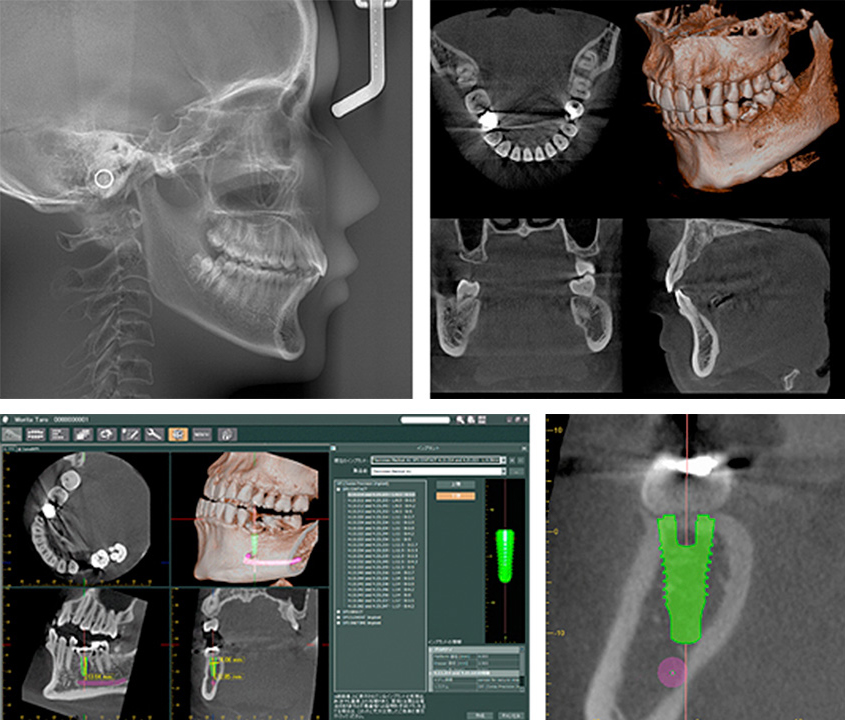

歯科治療を行うにあたり、まず顎の骨、歯周組織、血管や神経などの状態を正確に把握する必要があります。当院では、制度の高い治療を可能にするため、少ない放射線量で高品質な画像が得られる歯科用CT「Veraviewepocs 3Df」ベラビューエポックス3Dfを導入しています。

ベラビューエポックス3Dfは、従来の2次元でのレントゲン撮影に加え、3次元(立体的)画像で口腔内の状態を撮影をできます。また、様々な画像処理による多角的な観察が可能で、正確な情報に基づく的確な診査・診断が行えますので、安全性を飛躍的に高める事ができます。

ベラビューエポックスシリーズの最高位機種であるベラビューエポックス3Dfは、1台でパノラマ撮影、CT撮影、セファロ撮影が可能ですので、インプラント治療はもちろん、根管治療、歯周病治療など、様々な症例に活用できます。

● インプラント治療での活用

インプラント治療は、顎の骨に人工歯根を埋め込むため、術前の骨の厚みや質などの状態把握、人工歯根の埋入位置の決定、術後の状態確認が必要となります。これらすべての行程において、歯科用CTの3D画像で得られる、正確な情報は精密で正しく安全な治療に貢献します。

● 矯正治療での活用

搭載するセファロ機能は世界基準の頭部を基準にした歯の傾き、顎骨状態、歯の角度や歯列を正確に把握できますので、予知性の高い治療計画の立案が可能となります。